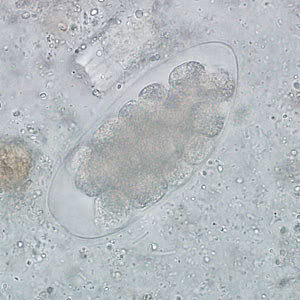

Trichostrongylus spp. eggs in wet mounts.

Trichostrongyle eggs in wet mounts.

Microscopic identification of eggs in feces is evidence of infection. Because eggs may be difficult to find in light infections, a concentration or flotation procedure is recommended. Patients may have co-infections with hookworm, so care must be taken to differentiate the two.